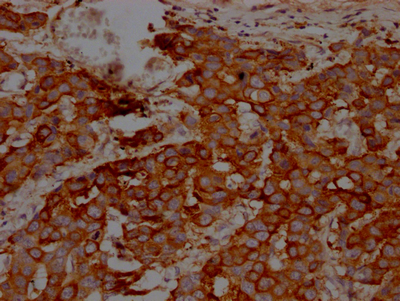

• IHC image of CSB-RA256500A0HU diluted at 1:100 and staining in paraffin-embedded human breast cancer performed on a Leica BondTM system. After dewaxing and hydration, antigen retrieval was mediated by high pressure in a citrate buffer (pH 6.0). Section was blocked with 10% normal goat serum 30min at RT. Then primary antibody (1% BSA) was incubated at 4℃ overnight. The primary is detected by a Goat anti-rabbit IgG polymer labeled by HRP and visualized using 0.05% DAB.